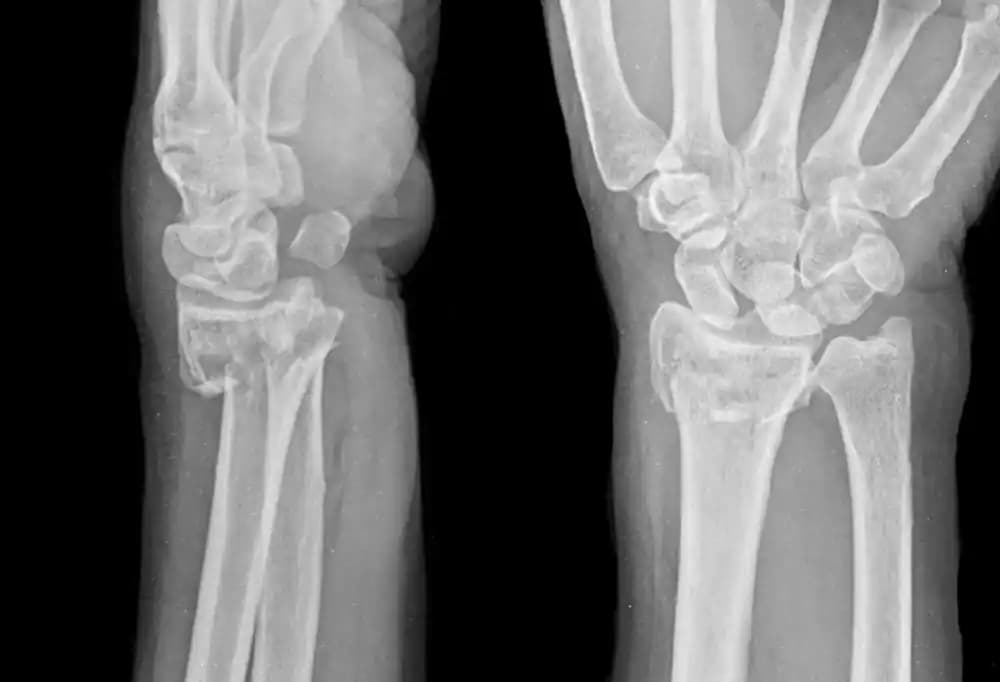

Radius Kırığı

Radius kırığı genellikle ileri yaştaki hastalarda görülmektedir. Ön kol ekleminin bir parçası olan Radius kemiği,...